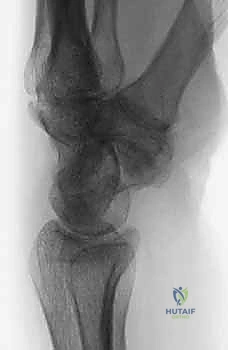

متلازمة SNAC (Scaphoid Nonunion Advanced Collapse) هي حالة تدهور تدريجي ومأساوي لمفصل الرسغ. تبدأ القصة بكسر في العظم الزورقي (غالباً بسبب السقوط على يد ممدودة). إذا لم يتم تشخيص هذا الكسر أو لم يلتئم بشكل صحيح، فإن العظم الزورقي ينقسم إلى قطعتين تتحركان بشكل غير طبيعي ومستقل عن بعضهما البعض.

هذه الحركة غير الطبيعية تخلق احتكاكاً مستمراً (Micro-trauma) مع العظام المجاورة، وتحديداً عظم الكعبرة (Radius). بمرور الوقت (أشهر أو سنوات)، يؤدي هذا الاحتكاك إلى تآكل الغضاريف الناعمة التي تغطي العظام، مما يسبب خشونة مفصلية شديدة (Osteoarthritis).

* التشخيص الخاطئ: بعض كسور الزورقي لا تظهر بوضوح في صور الأشعة السينية (X-ray) العادية في الأيام الأولى، وتتطلب أشعة مقطعية (CT) أو رنين مغناطيسي (MRI).

- الأشعة السينية الرقمية (Digital X-rays): بأوضاع متعددة (AP, Lateral, Scaphoid view) لتقييم زوايا العظام ودرجة الانهيار.

- الأشعة المقطعية (CT Scan): وهي المعيار الذهبي لتقييم حجم العظم المتآكل بدقة ثلاثية الأبعاد، وتحديد مدى الخشونة في المفاصل المحيطة.